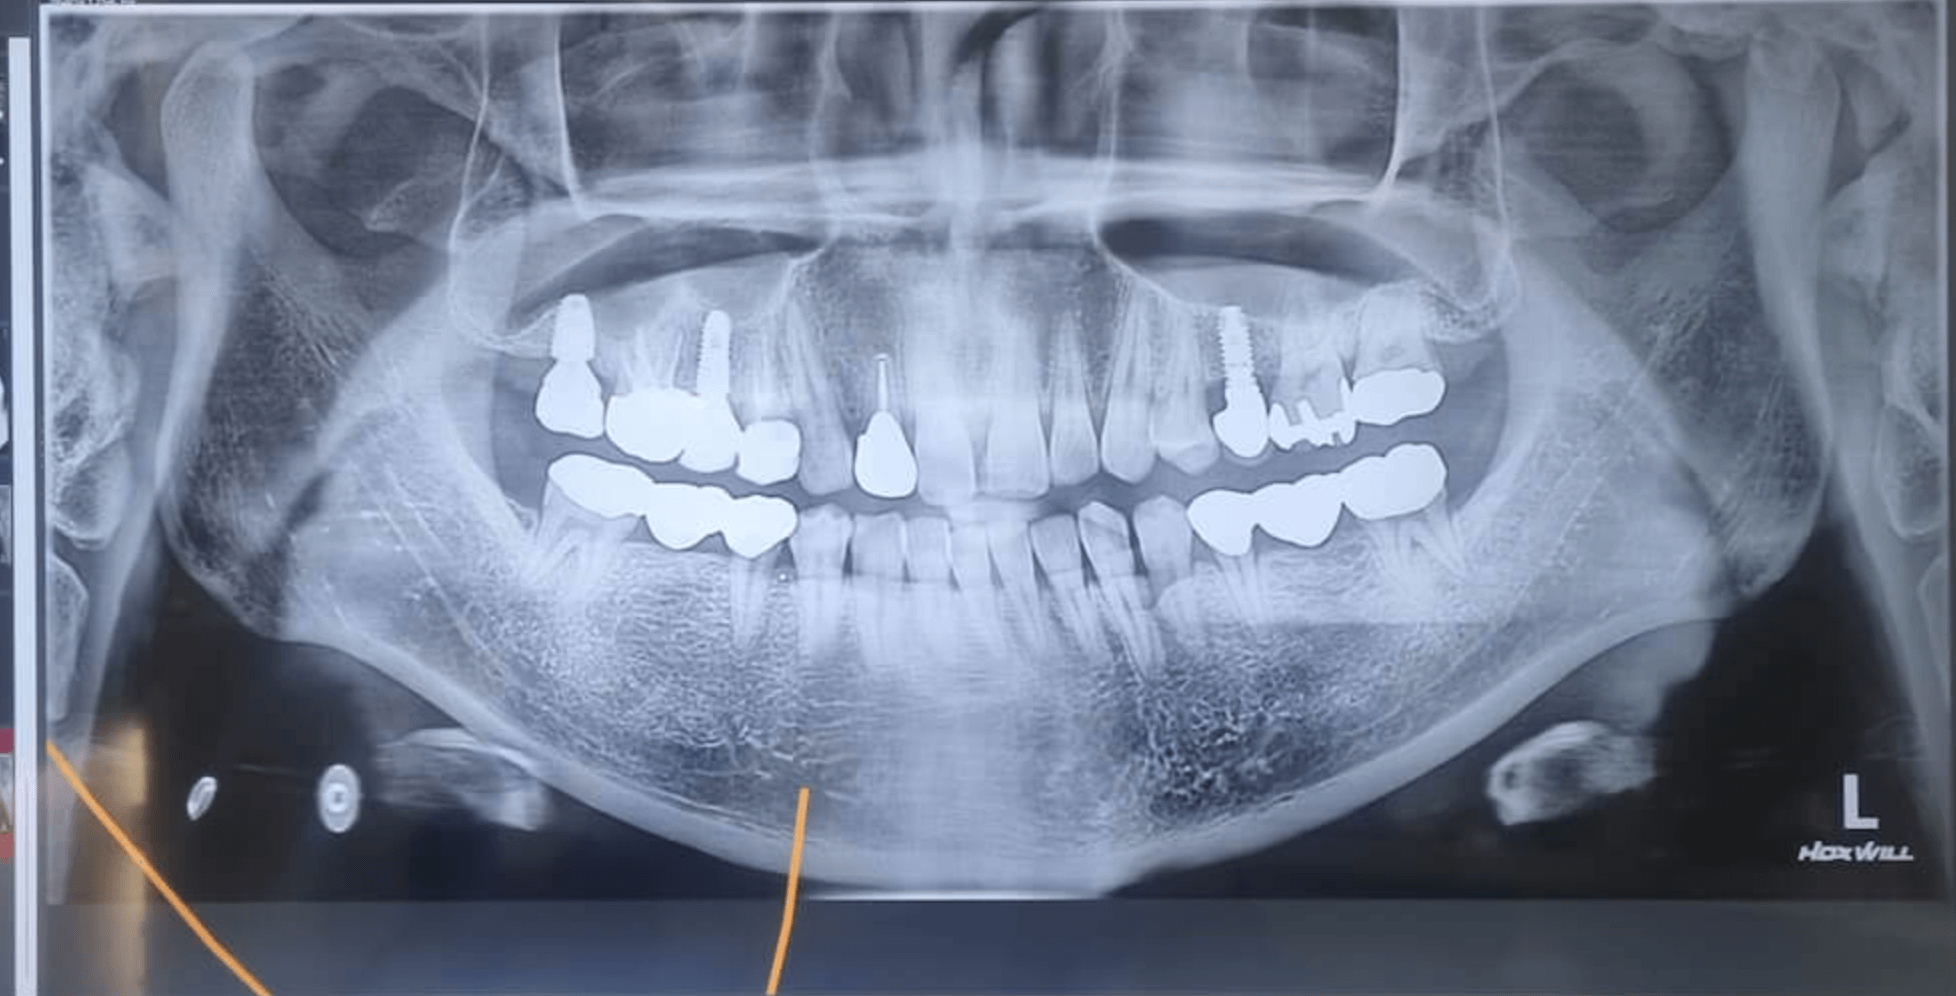

요즘 치과에 가면 대부분 지르코니아 크라운으로 하라고 추천을 해줍니다, 그런데 지르코니아가 강도가 강하다고 하지만 깨짐이 발생하지 않을까 그런 의문이 든다면, 해당 포스팅을 꼭 읽어보세요. 저는 지르코니아 브릿지 2번이나 금이 가버렸고, 지르코니아 깨짐이 발생하여 잇몸까지 베이며 지르코니아 강도를 믿지 않고 금니로 해야한다고 생각을 합니다.

저 또한 지르코니아 브릿지를 해넣은지 1년이 안되었는데 한번 금이가 버리고, 다시 지르코니아 브릿지로 A/S 받아해 넣었지만 몇 개월뒤 또 금이 가서 이번에는 아예 메탈 브릿지로 교체하여 삽입했습니다.

그런데, 이번에는 임플란트로 해넣은 맨 위 기둥 부분인 지르코니아 크라운이 음식을 씹다가 깨져버려서 잇몸이 베이고 주변 볼에 지르코니아 파편이 박혀서 2주 정도 고생을 한 것 같습니다.

이전에 지르코니아 브릿지가 금이 간 경우는 씹는 힘에 중심이 맞지 않아 깨질 수도 있다 생각을 했지만, 임플란트 기둥 위 지르코니아 크라운이 음식을 먹다가 깨져버리니 너무 화가 났습니다.

치과 의사 말로는 이런경우가 잘 없는데 정말 정말 죄송하다고 했습니다. 맨 뒤쪽 어금니라서 어차피 잘 보이지도 않는 부분이라 그냥 메탈로 해달라고 이야기를 했습니다.

글쓴이는 어릴때부터 치아가 별로 좋지 않아서, 최근 20-30년 지나다 보니 새롭게 해 넣어야 되는 치아들이 많았고, 염증으로 인해 임플란트를 해야 하는 경우가 자꾸 발생했습니다.

치과에서 보면 VIP 고객이라고 생각하면 될만큼 자주 치과를 방문했고, 지금도 이전에 치료했던 치아가 수명을 다해가는 게 많아서 쭈욱 치과 치료를 해야 합니다. 앞니 지르코니아 크라운 같은 경우는 크게 씹을 일이 없어서 깨짐이나 이런 것은 발생하지 않았습니다.